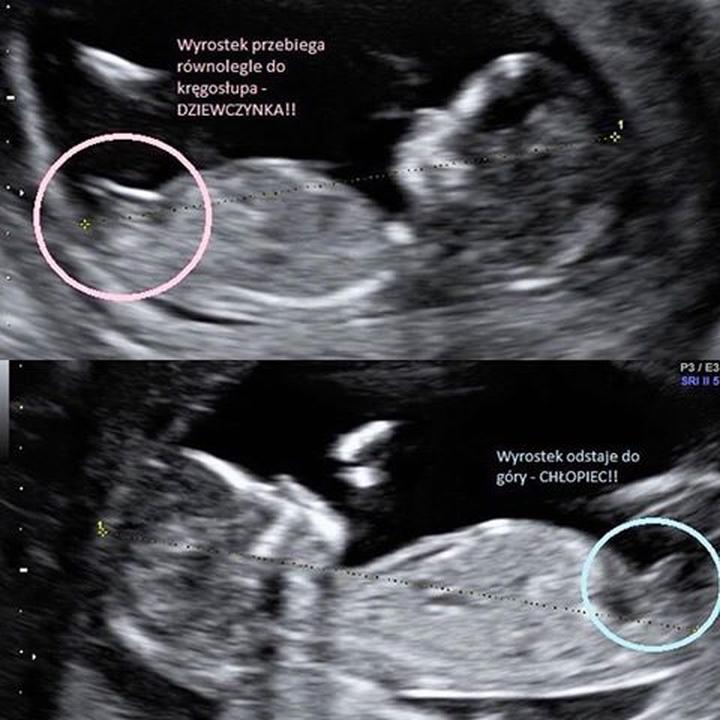

Kiedy zatem najlepiej zasięgnąć informacji o tym, kto naprawdę rozwija się w brzuchu mamy? W tej sprawie z pomocą przychodzi współczesna technologia, a mianowicie USG. W badaniach płeć można niewątpliwie określić z dużym prawdopodobieństwem między 18. a 22. tygodniem ciąży, a nawet wcześniej – w okolicach 12. tygodnia, gdy dziecko układa się w odpowiedniej pozycji. Badania pokazują, że w tym czasie można zauważyć guzki płciowe, które zapowiadają przyszłe narządy płciowe, ale powinniśmy być ostrożni – wczesne prognozy mogą się okazać mylne. A kto wie, może podczas oceny chirurgiczny majsterkowicz popełnił błąd?

Choć płeć dziecka ustala się w chwili zapłodnienia, to na USG można ją rozsądnie określić dopiero między 18 a 22 tygodniem ciąży. Wcześniej, w okolicach 12 tygodnia, możliwe jest czasami zauważenie guzka płciowego, jednak prognozy te mogą być jeszcze niepewne.